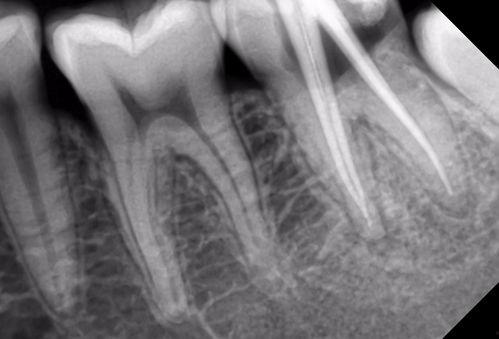

首先,得先弄清楚什么是根管治疗。简单来说,根管治疗就是治疗牙髓炎、根尖周炎等牙髓疾病的一种方法。当牙齿内部的神经和血管受到感染或损伤时,就需要进行根管治疗,将感染的牙髓清除,然后用药物填充根管,防止感染再次发生。

我看了几个根管治疗视频,发现治疗过程其实并不复杂。首先,医生会用局部麻醉剂让你放松,然后使用特殊的工具清除牙髓。这个过程可能会有些不适,但麻醉剂会帮你减轻疼痛。

视频里展示了各种治疗工具,比如根管锉、根管探针等。这些工具看起来有点吓人,但医生会小心翼翼地使用它们,确保治疗过程顺利进行。